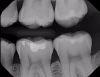

Transillumination technology bathes the tooth in safe, near-infrared light, which makes the enamel appear transparent. This allows clinicians to see through the tooth, exposing its structure and allowing for highly accurate detection of the structure of any carious lesions. In porous tissue such as lesions, the light is trapped and absorbed. Images using transillumination technology are similar to X-rays, with lesions appearing as dark areas and healthy tooth structure as light areas (Figure 1). Therefore, this familiarity facilitates interpretation. In addition, NIR results are not affected by the presence of bacteria, and calibration is not required, as it is with other devices.2

Fig 1. Example of image taken with transillumination technology. The dark area indicates caries.

Figure 1